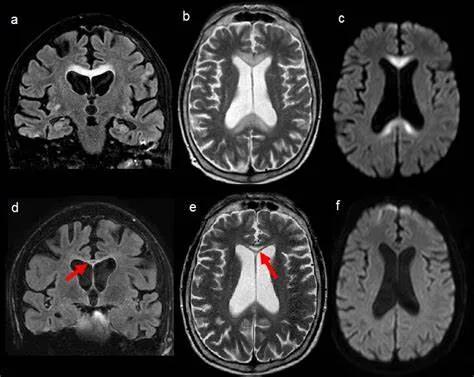

31岁,男性,长期饮酒,出现急性失语、短期注意力和记忆力缺陷,胼胝体及半卵圆中心对称性异常信号,扩散受限,未见强化,经过维生素B1/6/9/12治疗后病灶吸收明显,诊断为原发性胼胝体变性急性期。

48岁,男性,长期饮酒过量20年,出现出现眩晕,胼胝体、侧脑室周围白质、内囊后肢对称性异常信号,扩散受限,诊断为原发性胼胝体变性急性期。

胼胝体压部病变及多发皮层对称性病变,表现为扩散受限